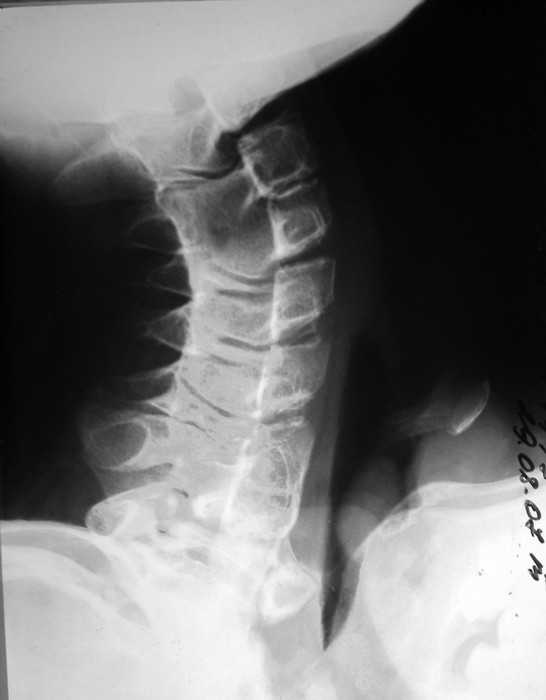

Вложение не в текстовом формате было извлечено…

Имя     : neck07.JPG